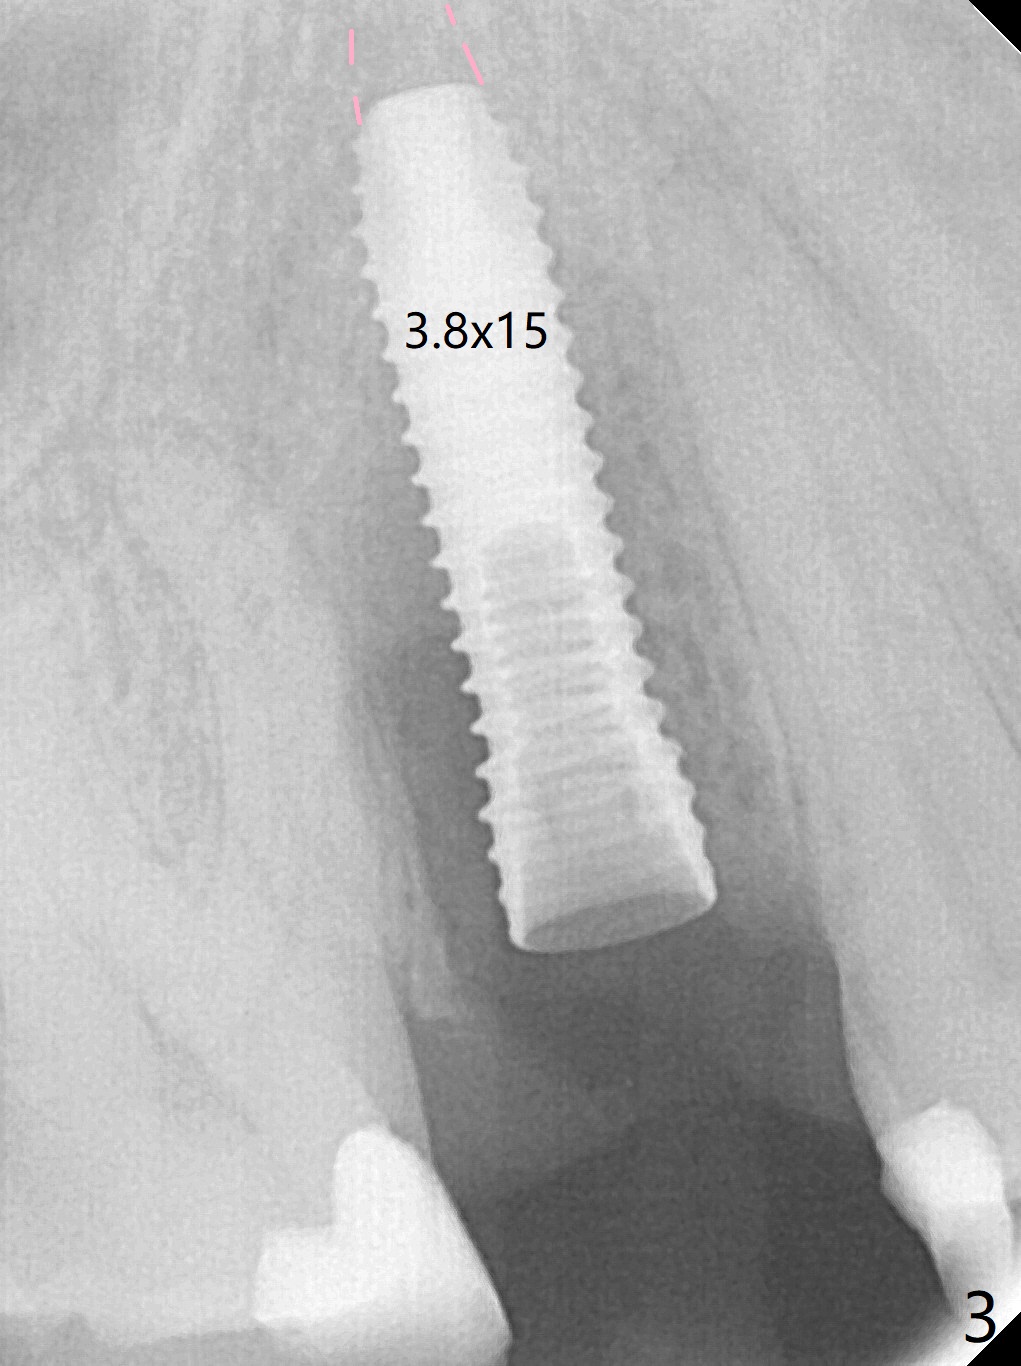

When the tooth #4 with vertical root fracture (Fig.1) is extracted, the buccal plate is found to be lost. The lowest point of the defect is shown as black dashed line in Fig.2 (yellow dashed line: sinus floor). After use of 2.5 mm reamer for 21 mm (buccal gingival level) and 3.0 mm reamer for ~17 mm, a 3.8x15 mm dummy implant is placed with 30 Ncm and 1.85 mm apical space (Fig.3 pink outline). A 3.8x18 mm (definitive) implant is placed with <40 Ncm with the implant plateau apical to the lingual crest (Fig.4,5). The buccal plate defect is repaired by Vanilla Graft (Fig.6 *) before and after insertion of a 4.5x4(3) mm abutment. The buccal plate defect seems to being repaired 4 months postop (Fig.7). Occlusal wear suggests bruxism, which is also associated with the root fracture. Night guard is recommended. The defect repair is close to completion 8 months post cementation (Fig.8). The crown/abutment is found to be loose 1 year 4 months post cementation and retightened without checking whether there is clinical 2nd DO caries of #3 (Fig.9, "sensitive to water pik"). A few days later, DO composite is being removed. It is difficult to determine whether the 2nd DO caries or gap has been removed with the neighboring crown in place. When the crown/abutment is removed and gingival retractions are inserted, there is no decay. The gap is removed. With Toflemire in place, the crown/abutment is reseated and hand tightened; after packable composite, the crown/abutment is removed, there is no more DO gap.